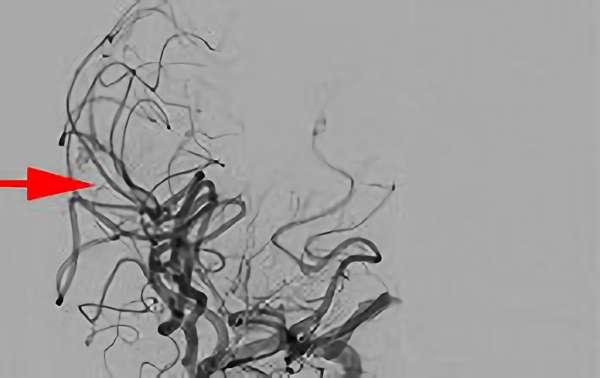

No.1583 手術前

No.1583 手術中

No.1583 手術後

'25年10月

脳動静脈奇形

60代

大阪府の病院